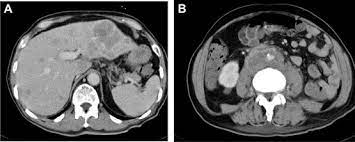

Texas Soc Of Pathol On Twitter Metastatic Prostate Carcinoma Patients With Liver Metastases Have Worst Median Overall Survival In Prostate Cancer Cases Most Common Prostate Cancer Metastases In Vertebrae And Other Bones

Texas Soc Of Pathol On Twitter Metastatic Prostate Carcinoma Patients With Liver Metastases Have Worst Median Overall Survival In Prostate Cancer Cases Most Common Prostate Cancer Metastases In Vertebrae And Other Bones from pbs.twimg.com